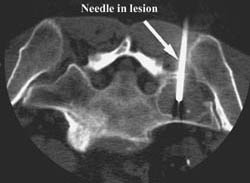

Sacral biopsies can be performed with CT guidance. In the images below the lesion was a hemangioma but there was suspicion for a more aggressive process.